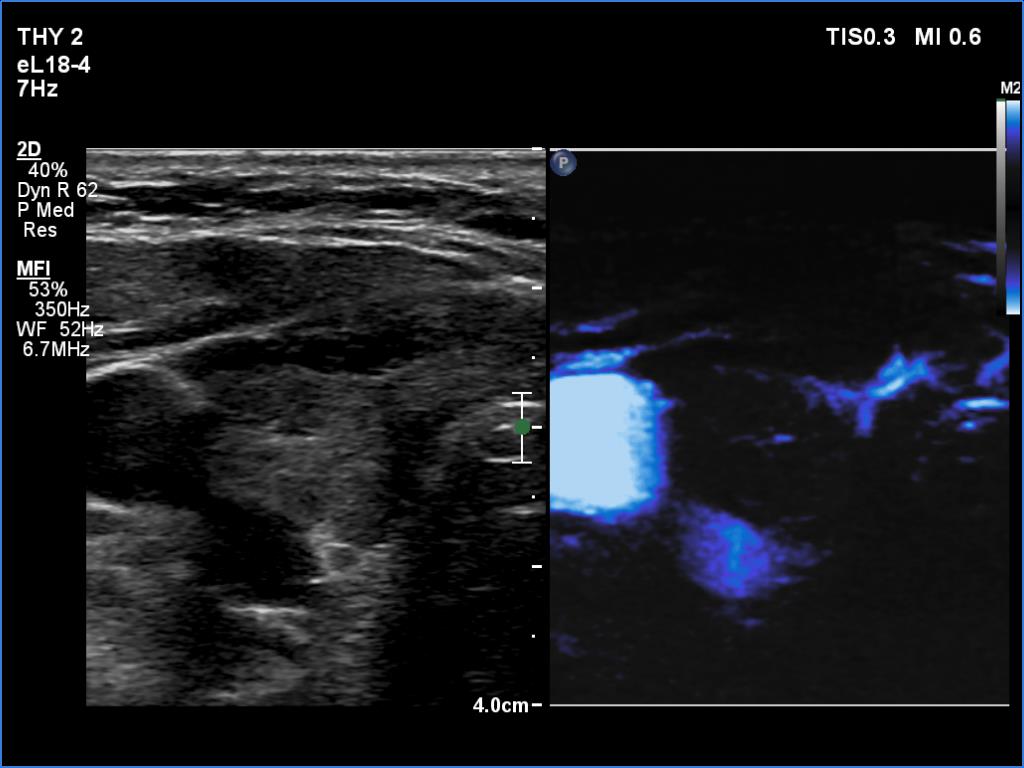

Ultrasonography. The thyroid was hypoechogenic. There was an iso/hyperechoic nodule in both the right and left lobes. The nodule in the left lobe had perinodular vascularity. The dimensions of the nodule in the left lobe were 20x18x31 mm, width, depth, length, respectively. This means that the volume of the nodule has increased almost 8-fold in 10 years.